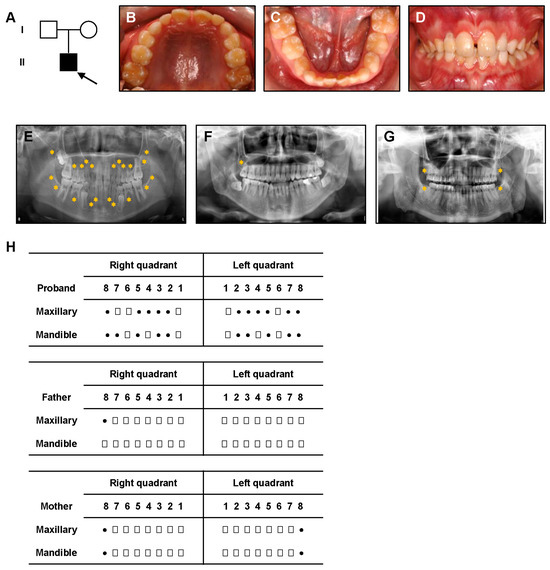

3.1. Clinical Manifestations

| Subject | Genotype | Phenotype |

|---|---|---|

| Proband | c.1657_1660delinsA | NSTA; absence of 17 permanent teeth |

| Father | Wild-type | Absence of 1 third molar (within normal variation) |

| Mother | c.1657_1660delinsA | No clinical anomalies; absence of third molars (within normal variation) |